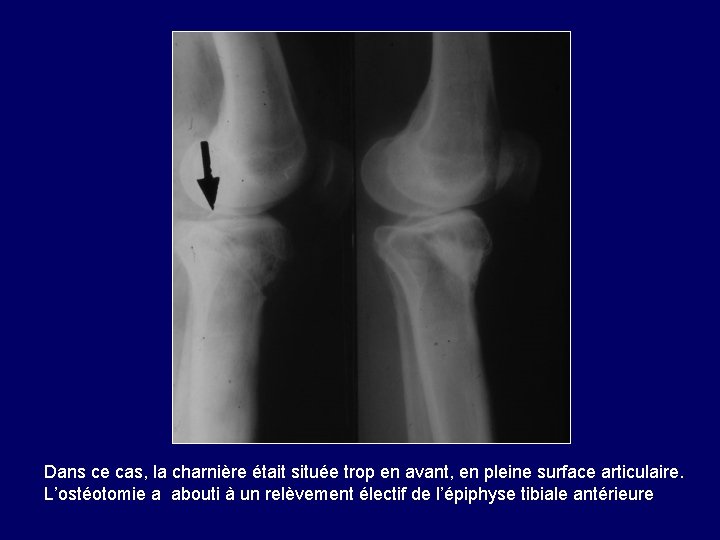

Dans ce cas, la charnière était située trop en avant, en pleine surface articulaire. L’ostéotomie a abouti à un relèvement électif de l’épiphyse tibiale antérieure